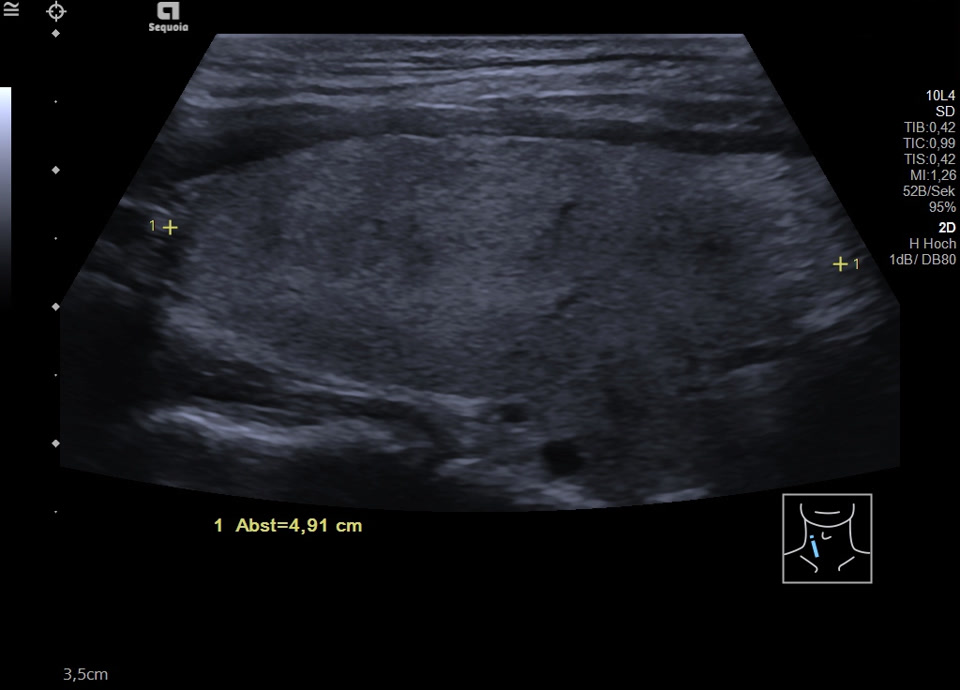

45-year-old male presented patient with persistent sore throat and general symptoms following an EBV-infection. An external diagnosis of post-infectious de Quervain’s thyroiditis had already been made, and a two-week course of corticosteroid therapy was administered. Initial clinical improvement with reduced throat pain was noted under treatment, but symptoms reoccurred after discontinuation of corticosteroids. Laboratory findings revealed leukocytosis of 12,000/µl and CRP of 113 mg/l. Sonographically, a bilaterally enlarged thyroid gland with diffusely hypoechoic areas and inhomogeneous parenchyma was observed. Combined with the patient history, this was characteristic of a subacute thyroiditis with relapse after short-term corticosteroid therapy. Prolonged corticosteroid therapy with slow tapering was performed. Under this regimen, marked clinical improvement occurred within weeks; follow-up ultrasound four months later showed a normal-sized thyroid with only mildly inhomogeneous parenchyma, consistent with resolving thyroiditis.